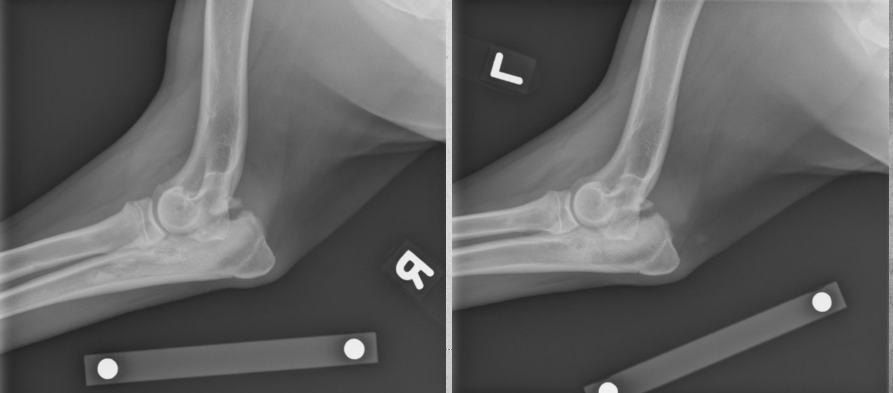

3 month old kitten

Sudden onset lameness of left front leg

Fracture through the lateral distal humeral physis with mild cranial displacement of the humeral condyle in relation to the proximal humeral fracture fragment.

Soft tissue swelling.